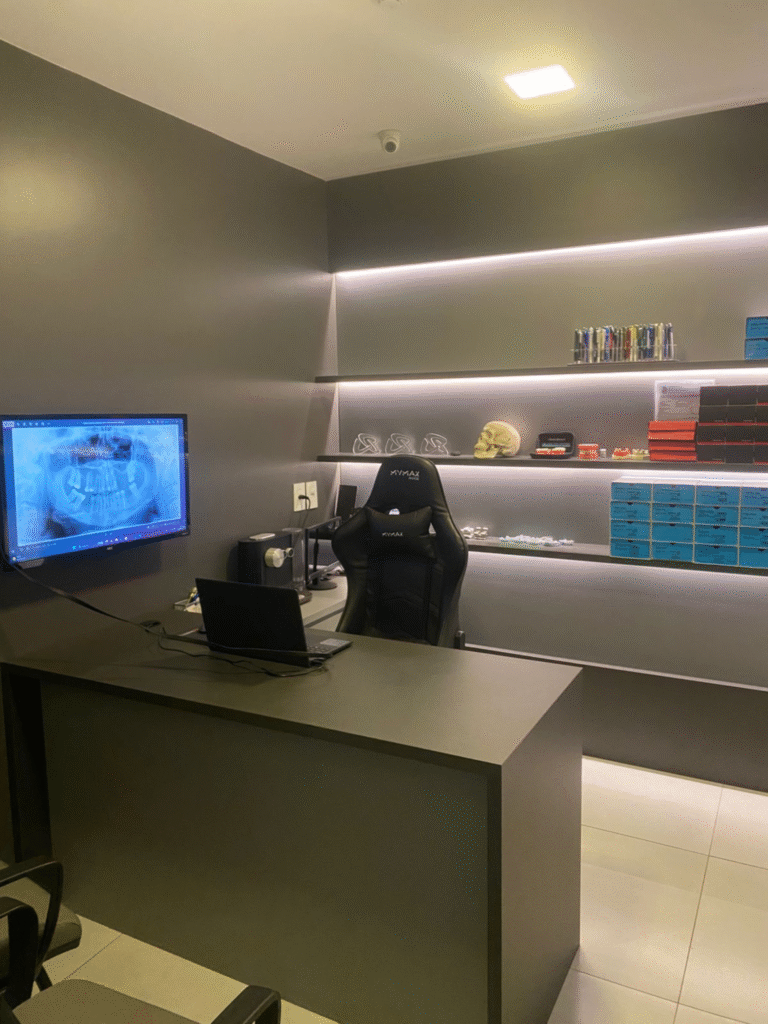

Agora contamos com o scanner intraoral mais avançado do mercado.

Com imagens 3D ultra precisas e escaneamento super rápido, seus tratamentos são mais confortáveis e personalizados desde o primeiro atendimento.

Nossa Clínica

A melhor clínica de São Caetano do Sul (SP) para transformar o seu sorriso